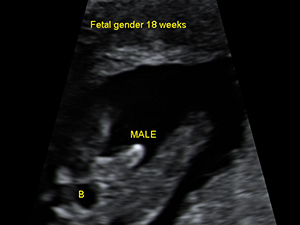

Gender - Male

Male genital organ (arrow) at 18 weeks